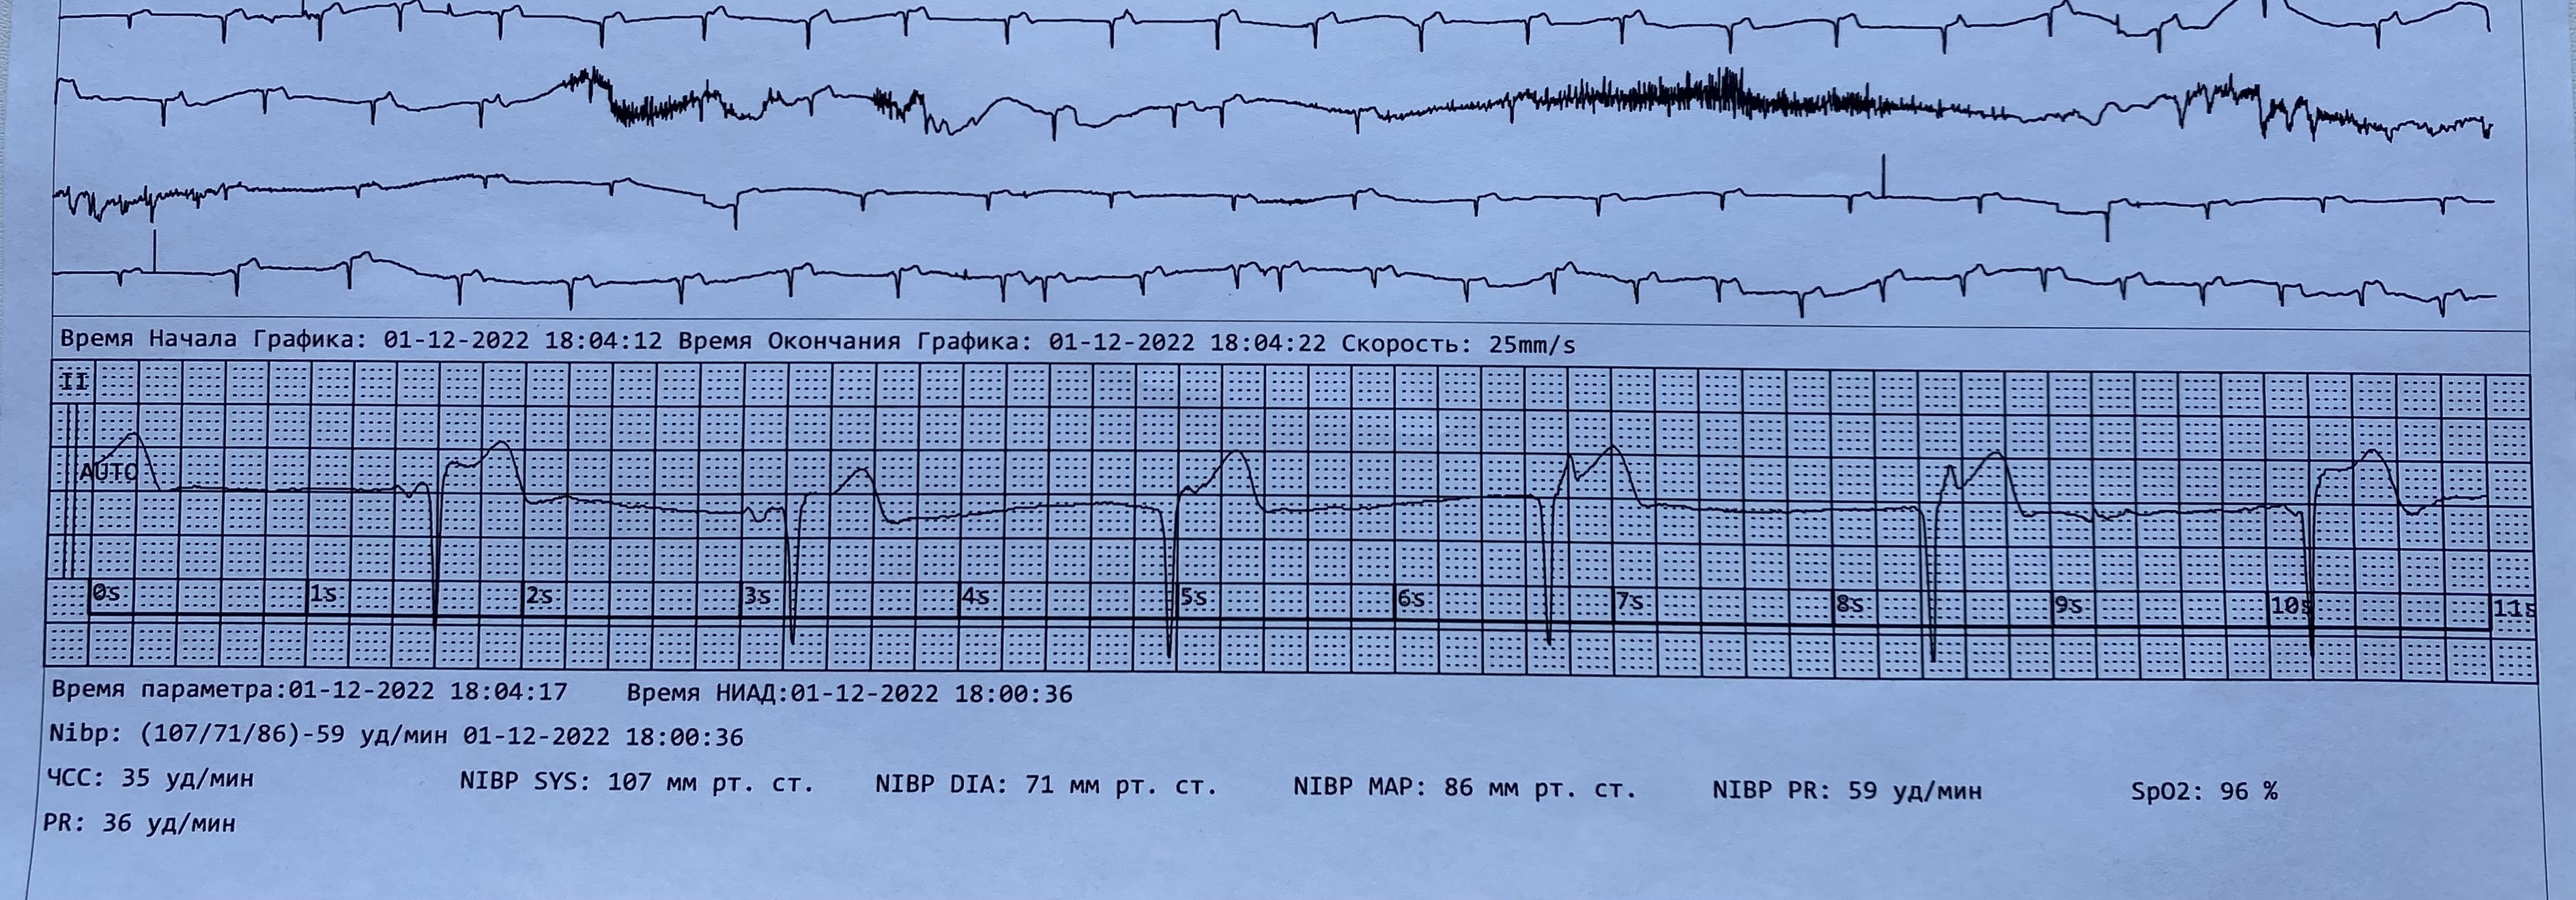

Предсердный переходит в изоритмическую АВ диссоциацию

Обсуждалось здесь https://vk.com/club84409679?w=wall-84409679_13425%2Fall